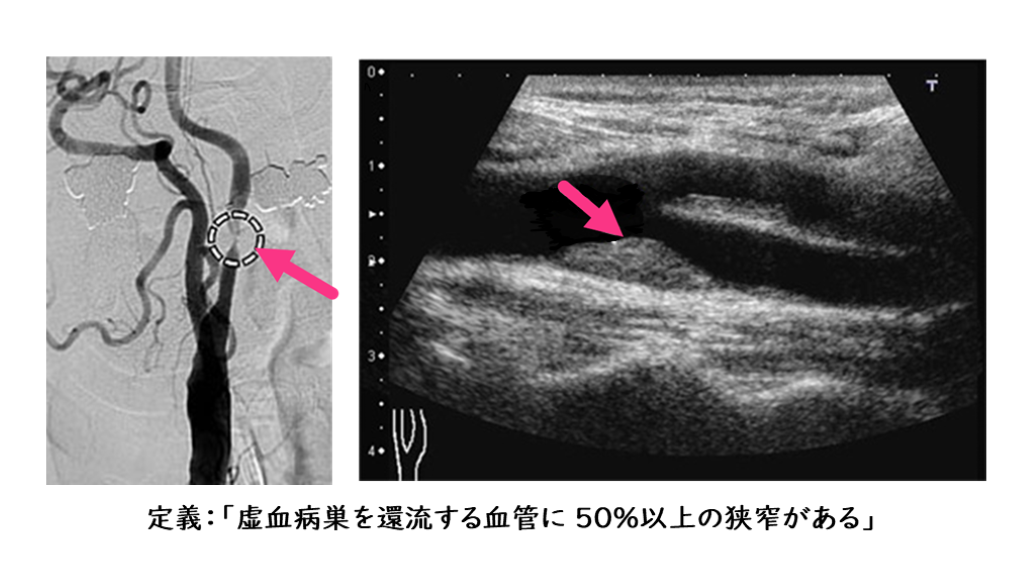

アテローム血栓性脳梗塞の発症機序

主幹動脈狭窄が原因で、それより遠位の血流領域に虚血を来しうる。

定義:「虚血病巣を還流する血管に 50%以上の狭窄がある」